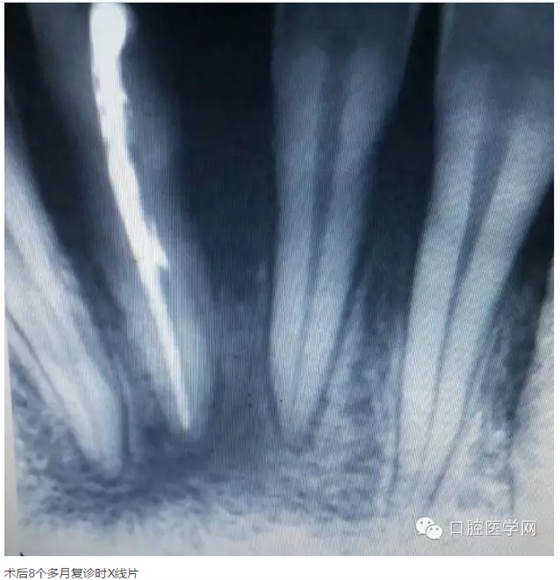

下面是一例 今年年初治療的下前牙根尖囊腫病例,患者因故未能按時復(fù)診,最近才來。